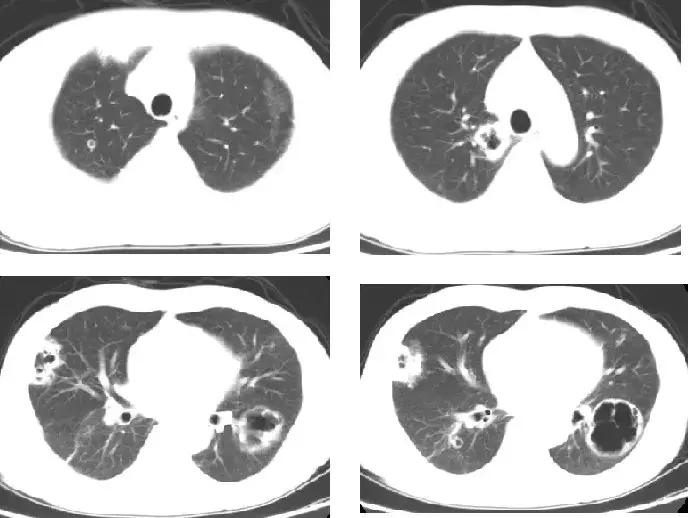

入院前胸部CT(当地上级医院2015-5-3)

1月前(2015-4-6),患者无明确诱因出现咳嗽、咳脓血性痰,量少,约5ml/天,伴右侧胸部持续性针刺样疼痛,可忍受,咳嗽、深呼吸时疼痛明显,与进食、活动无明显关系,无放射痛,无发热、畏寒、潮热、盗汗,无呼吸困难、心悸、心前区压榨样疼痛,无腹痛、腹泻。患者未予重视,后右侧胸痛逐渐加重,于2015-4-13至当地医院就诊,胸部CT提示「双肺多发结节影,部分可见空洞」,诊断「肺部阴影待查」,予「头孢类」抗菌素治疗10余天,上述症状无明显缓解,遂于2015-4-26至当地上级医院就医,胸部CT(2015-5-3)提示「双肺多发病灶并空洞形成」,行CT引导下经皮肺穿刺活检术。在等待穿刺病理结果期间予抗感染、止血等治疗(具体不详),上述症状仍无缓解。为进一步诊治于5月6日就诊我院呼吸门诊,以「双肺空洞待查」收入病房。